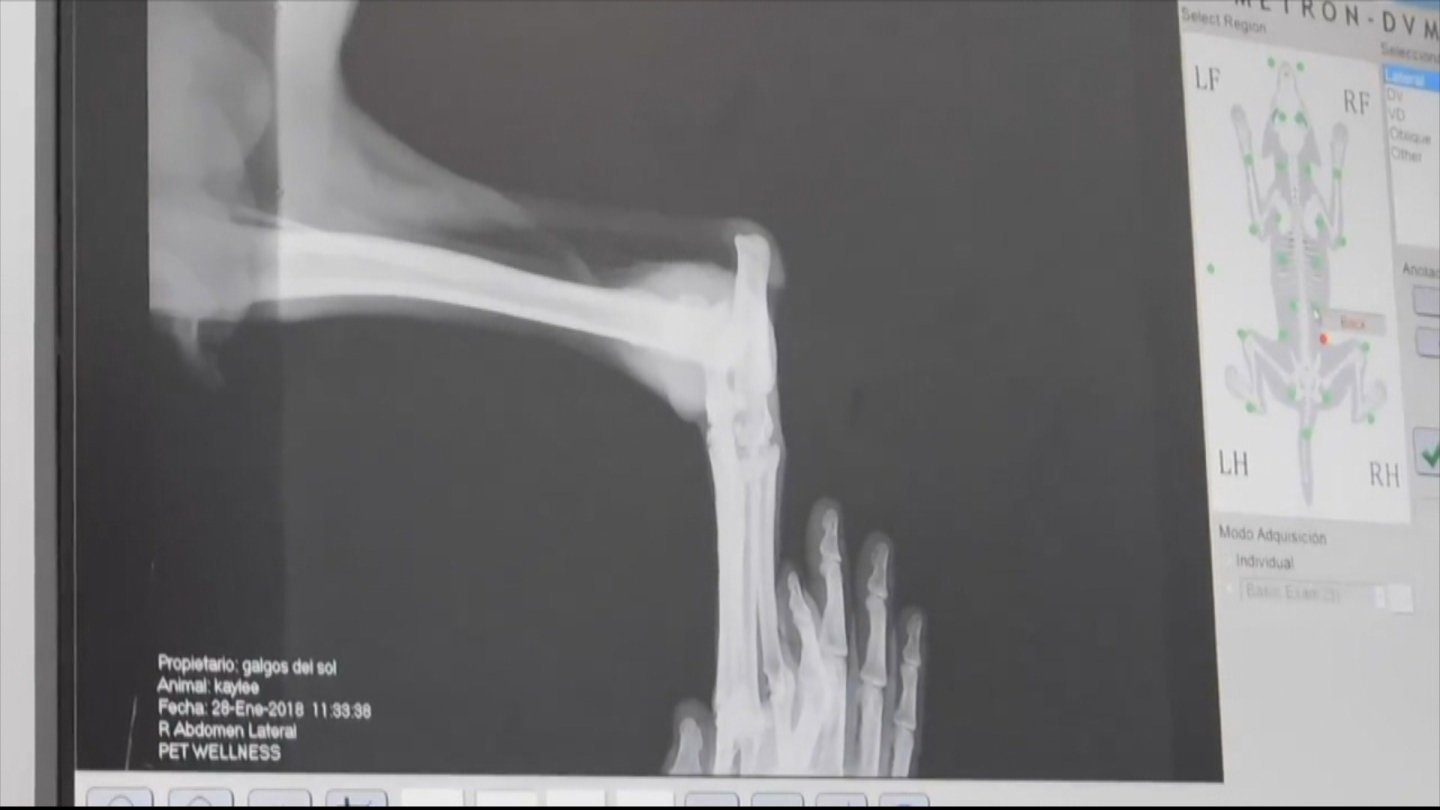

Fracturas, maltratos y abandono animal fueron algunas de las revelaciones parte de un reportaje de CHV Noticias sobre cómo viven los perros galgos que son usados en carreras clandestinas en Chile.